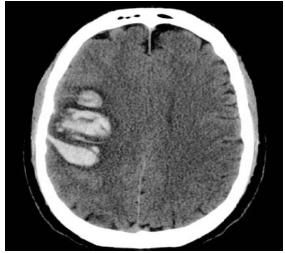

Paciente de 65 anos, do sexo masculino, com antecedente de hipertensão arterial mal controlada e diabetes, é admitido na UTI com o diagnóstico de acidente vascular cerebral hemorrágico de etiologia hipertensiva.

Ao ser admitido, apresenta-se em Glasgow 15, hemiplégico à direita, disártrico e com paralisia facial de padrão central, sem outras alterações ao exame neurológico. Encontra-se ainda com FC 65, PA 190x110, FR 18, SatO2 97% em ar ambiente e com glicemia capilar de 350mg/dL.

A imagem a seguir ilustra uma tomografia de crânio realizada no Pronto Socorro.

Na prescrição deste paciente da UTI devem constar os seguintes itens, à exceção de um. Assinale-o.